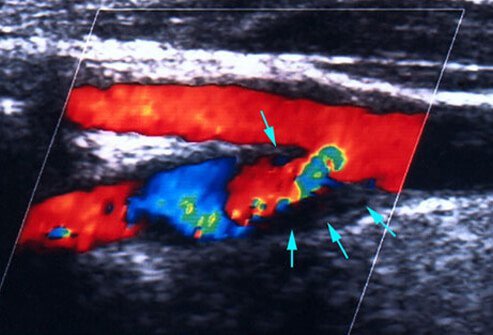

Preventing Another Stroke: Surgery

There are some surgical options for stroke prevention. Some patients have plaque- narrowed carotid arteries. The plaque can participate in clot formation in the artery and can even shed clots to other areas in the brain’s blood vessels. Carotid endarterectomy is a surgical procedure in which the surgeon removes plaque from the inside of the arteries to reduce the chance of strokes in the future.